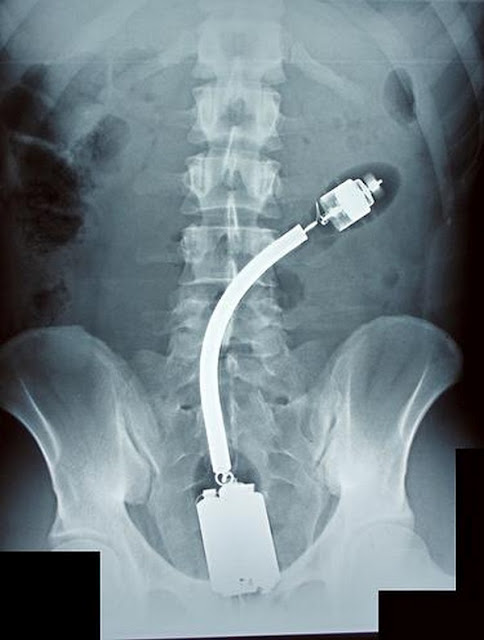

Foto X-Ray Objek Aneh Tertinggal Dalam Organ Intim

mak aih...nak besar sangat, paip besi terbuang ada kat bawah nun...ade paip bocor pagi tadi..syabas dh tukor..sila masuk dalam poen..pasti kesal  |

Apasal aku rasa macam photoshop ajer..... |

edit nih....ceh,...nk nipu je kje |

betul ke ni...mcm photoshop je  |